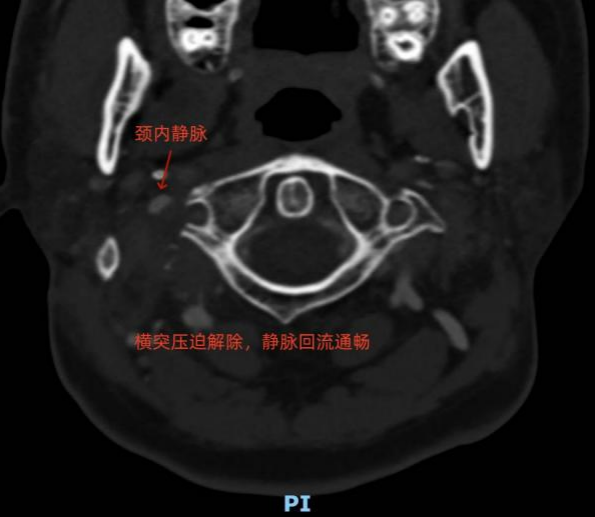

术后两周,患者脑鸣、头痛彻底消失;术后复查显示右侧颈内静脉压迫已完全解除,静脉恢复良好,血流在各种姿势下均通畅无阻。